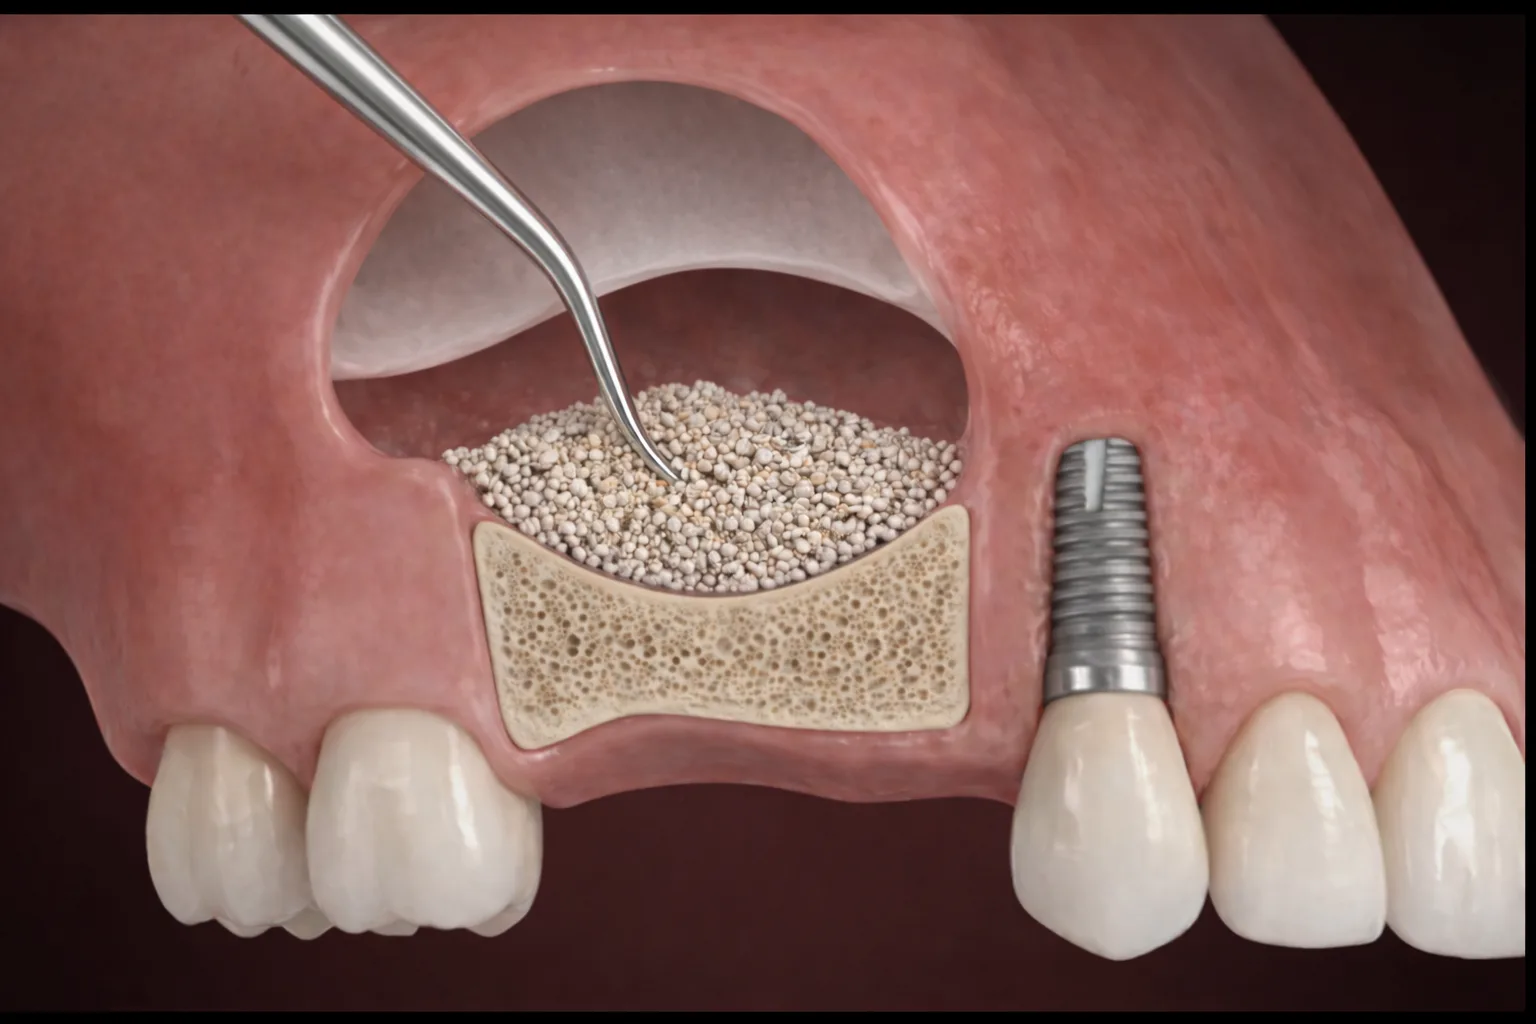

재수술은 기존 뼈 상태가 좋지 않은 경우가 많아 더 정밀한 진단과 섬세한 접근이 필요합니다.

임플란트가 실패한 부위는 뼈가 약해져 있거나 염증 흔적이 남아있는 경우가 많습니다. 따라서 재수술은 단순히 다시 심는 것이 아니라 원인을 정확히 찾고, 구조를 회복시키며, 다시 안정적인 상태로 만드는 과정이어야 합니다.